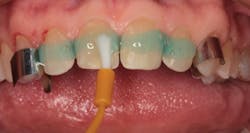

By carefully removing the veneers with fine diamond burs in a high-speed handpiece with water spray, I was able to minimize additional tooth structure removal, and no anesthetic was needed. Figure 3 shows the facial view after removal of the veneers. The incisal view can be seen in Figure 4. The patient decided that she wanted two additional veneers for her second premolars. Final impressions were taken, as well as a facebow record and occlusal registration. The patient chose Vita OM2 bleach shade as her desired color.

Figure 3: Facial view after removal of the veneers